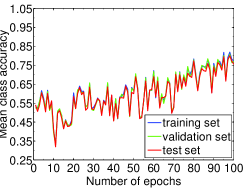

We highlight that training-relevant hyper-parameters can significantly affect the convergence of cost function, the learning speed and the generalization capability of the network. Their impacts are demonstrated via the learning curves of MCA on training, validation and test sets shown from Fig. 4 to Fig. 8. In each figure, we focus on one hyper-parameter while the others are set to their optimal values in Table 2.

Fig. 4 LABEL:sub@subfig:lr1 indicates that when learning rate is small, e.g., , the learning process is so slow that the MCA of the three sets have not become stable in epochs. Properly increasing the learning rate effectively improves learning efficiency and the MCA becomes stable in epochs, as shown in Fig. 4 LABEL:sub@subfig:lr2. At the same time, an over-large learning rate, e.g., , will destabilize the learning process and degrade the classification performance. Also, Fig. 5, 6 and 7 demonstrate the impacts of mini-batch size, momentum and weight decay, respectively.